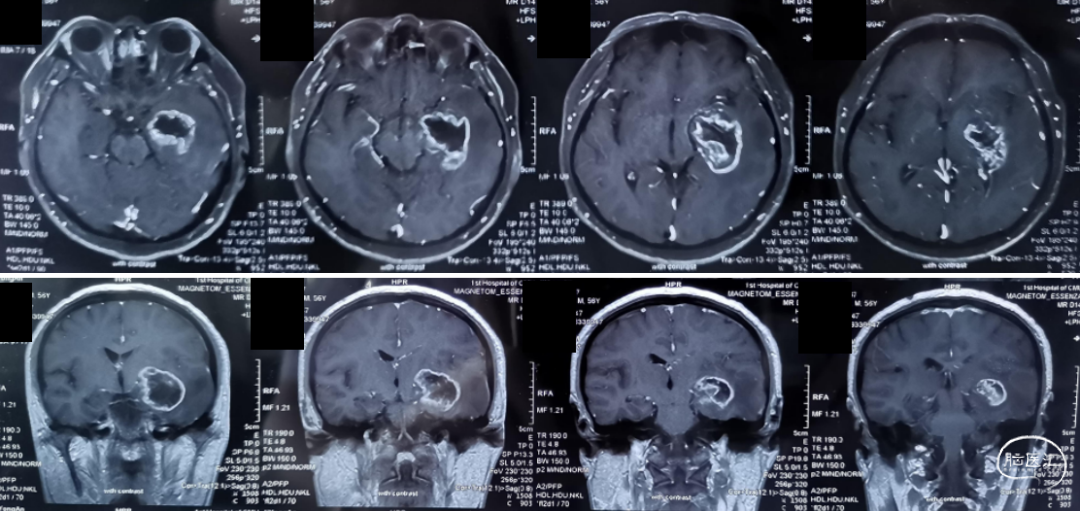

影像学资料

2020-04-26术前MRI:图示。

术后23天MRI对比:图示。

2020-07-20术后MRI(术后2.5个月,放疗后,TTFields治疗前):图示。

2020-10-15术后MRI(术后5月余,TTFields治疗后2个月):图示。

2021-01-26术后MRI(TTFields治疗后5.5个月):图示。

2021-04-22术后MRI(TTFields治疗后8个月):图示。

不同时期MRI对比:图示。